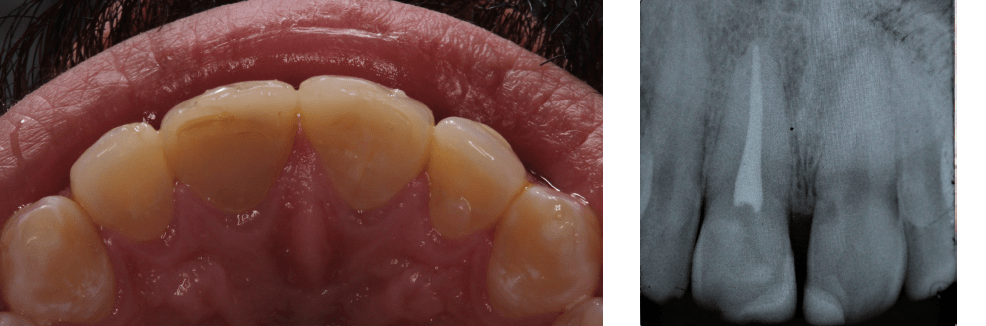

Endo Access clinical image 1 January 15, 2025 By celf_admin Endo Access clinical image 136 DownloadsDownload Now!